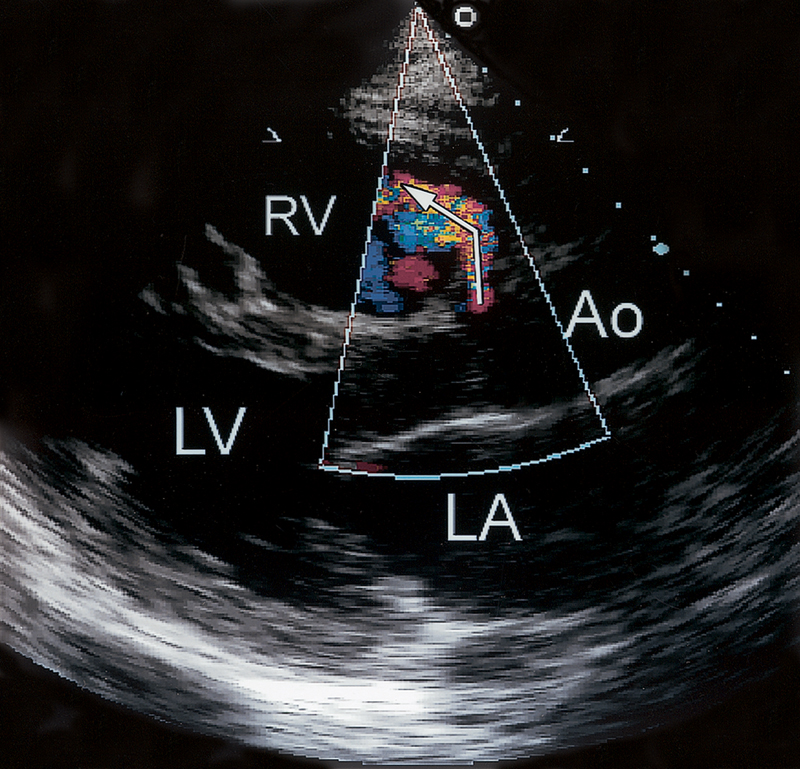

فحوصات تشخيصية لبعض امراض القلب والشرايين التاجية